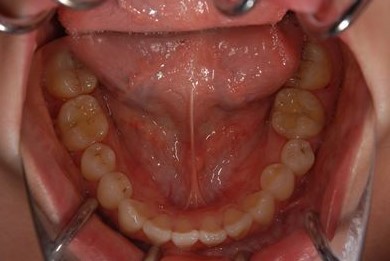

治療前

• 治療前